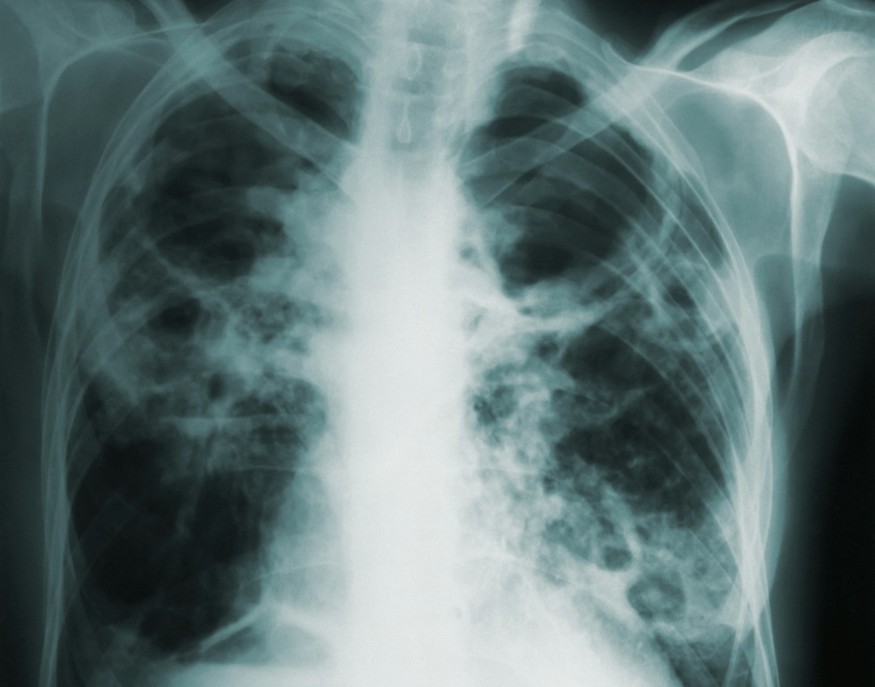

“Lung cancer is the leading cause of cancer death in Wales. Too often it is diagnosed late because it may not cause symptoms in its early stages. Screening gives us a chance to find it early, before symptoms appear.